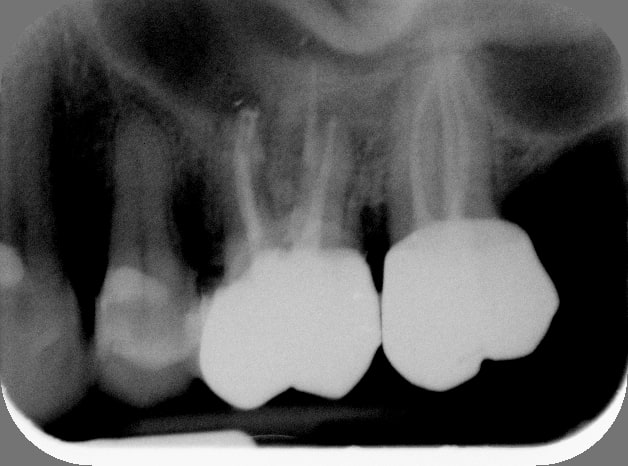

16/10/2014 à 18h16

Je l'ai déjà dit, c'est grâce à la séquence de chicot29 vaguement modifiée que je suis redevenu serein en endo.

A l'instant, en 1h, dépose cr et screw post 26, rtr, rcr collée et rescellement de la couronne en pro. Retour dans 3 mois pour l'empreinte. CA 250E, ça va c'est mon taux horaire.

Dixit la patiente: pourtant, c'était un praticien âgé, il avait l'air d'avoir de l'expérience.

Avant us1epm - Eugenol

Apr s ryhpr6 - Eugenol